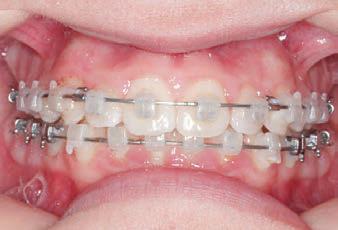

Fastrack your orthodontic treatments. Save 6 months or more.

The SAGITTAL FIRST™ Philosophy is a time-tested approach that standardises, simplifies, and shortens Class II and Class III treatment times. It employs the Carriere Motion 3D Appliance to treat the AP dimension at the beginning of treatment before placing brackets or aligners. By resolving the most difficult part of treatment first, you can achieve a Class I platform in 3 to 6 months, shortening total treatment time by a minimum of 6 months1. You know how excited patients and parents become when you mention shorter treatment times.

1 “Treatment Effects of the Carriere Distalizer (Motion 3D) Using Lingual Arch and Full Fixed Appliances”, Journal of the World Federation of Orthodontists, May 2014

CLASS II DIV.1 - Marra

INITIAL - 4/4/18

PROGRESS 1 - 26/9/18 - Class I platform accomplished in 5.75 months with Motion 3D COLOR Appliance

PROGRESS 2 - 26/9/18 - Placement of the SLX 3D Clear Brackets